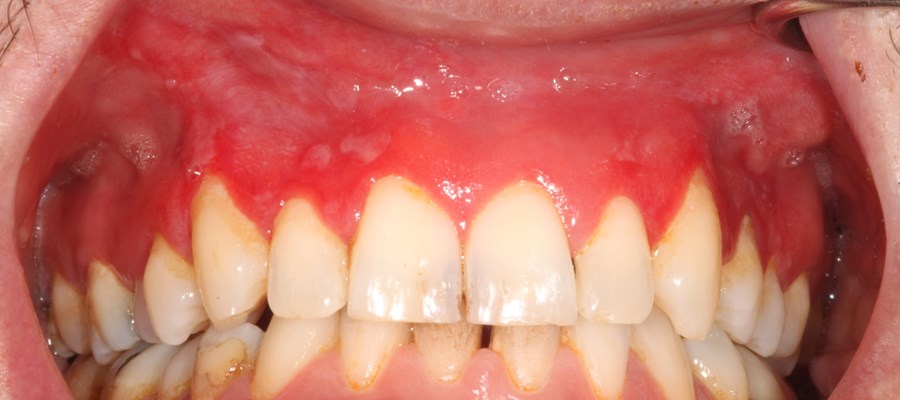

Vid användning av brunt snus blir slemhinnan oftast veckad och får en vit förtjockning där prillan läggs in. Hos vissa uppstår även sår där det vita snuset läggs mot slemhinnan. Vi är mer oroliga för de här förändringarna. De ser helt annorlunda ut, med rodnad och uttunnad slemhinna. Vävnadsprover har visat på kraftig inflammation och vi rekommenderar omedelbart snusstopp när man har besvär eller ser förändringar, säger Gita Gale, disputerad specialisttandläkare och en av forskarna bakom studierna.

Förändringarna vid användning av vitt snus tycks också vara mer svårläkta. Hos användare av brunt snus återställs tandkötet oftast på några veckor efter ett snusstopp. Skadorna efter vitt snus har visat sig kunna bestå i många månader, till och med uppemot något år.